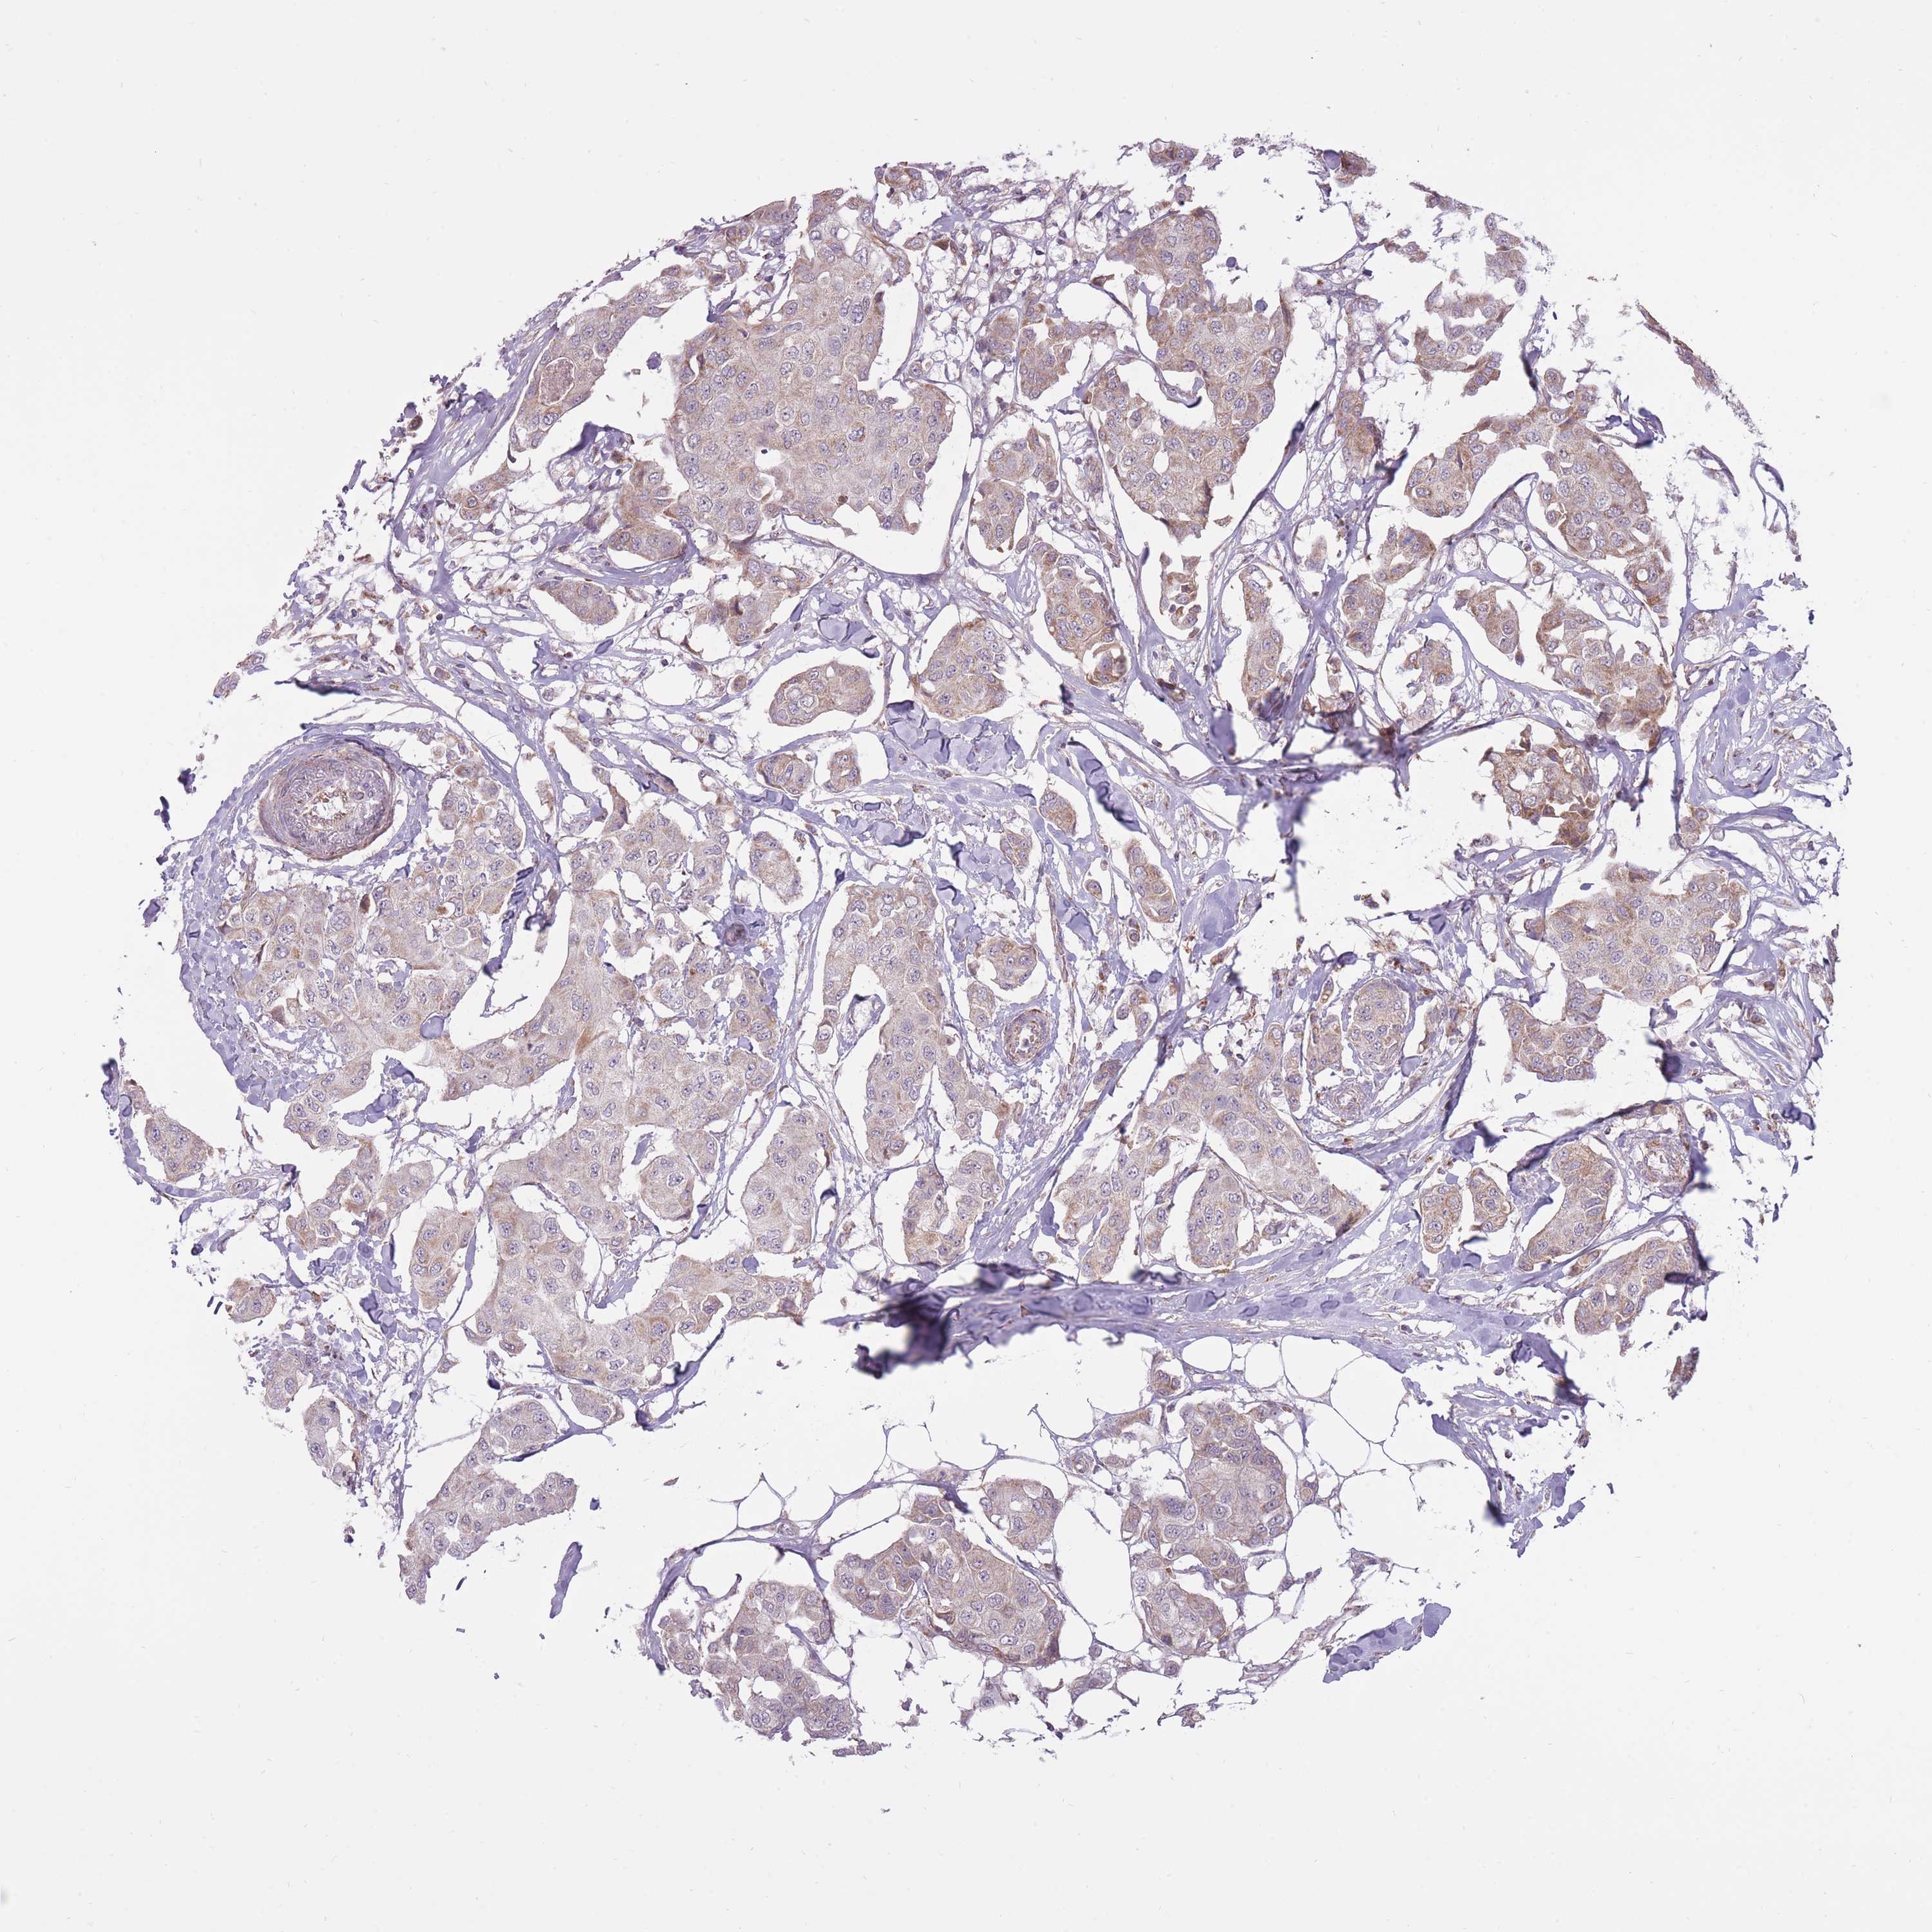

CANCER BREAST CANCER Show tissue menu

BRCA TCGA BRCA VALIDATION PROTEIN EXPRESSION

Breast cancer

Human cancer